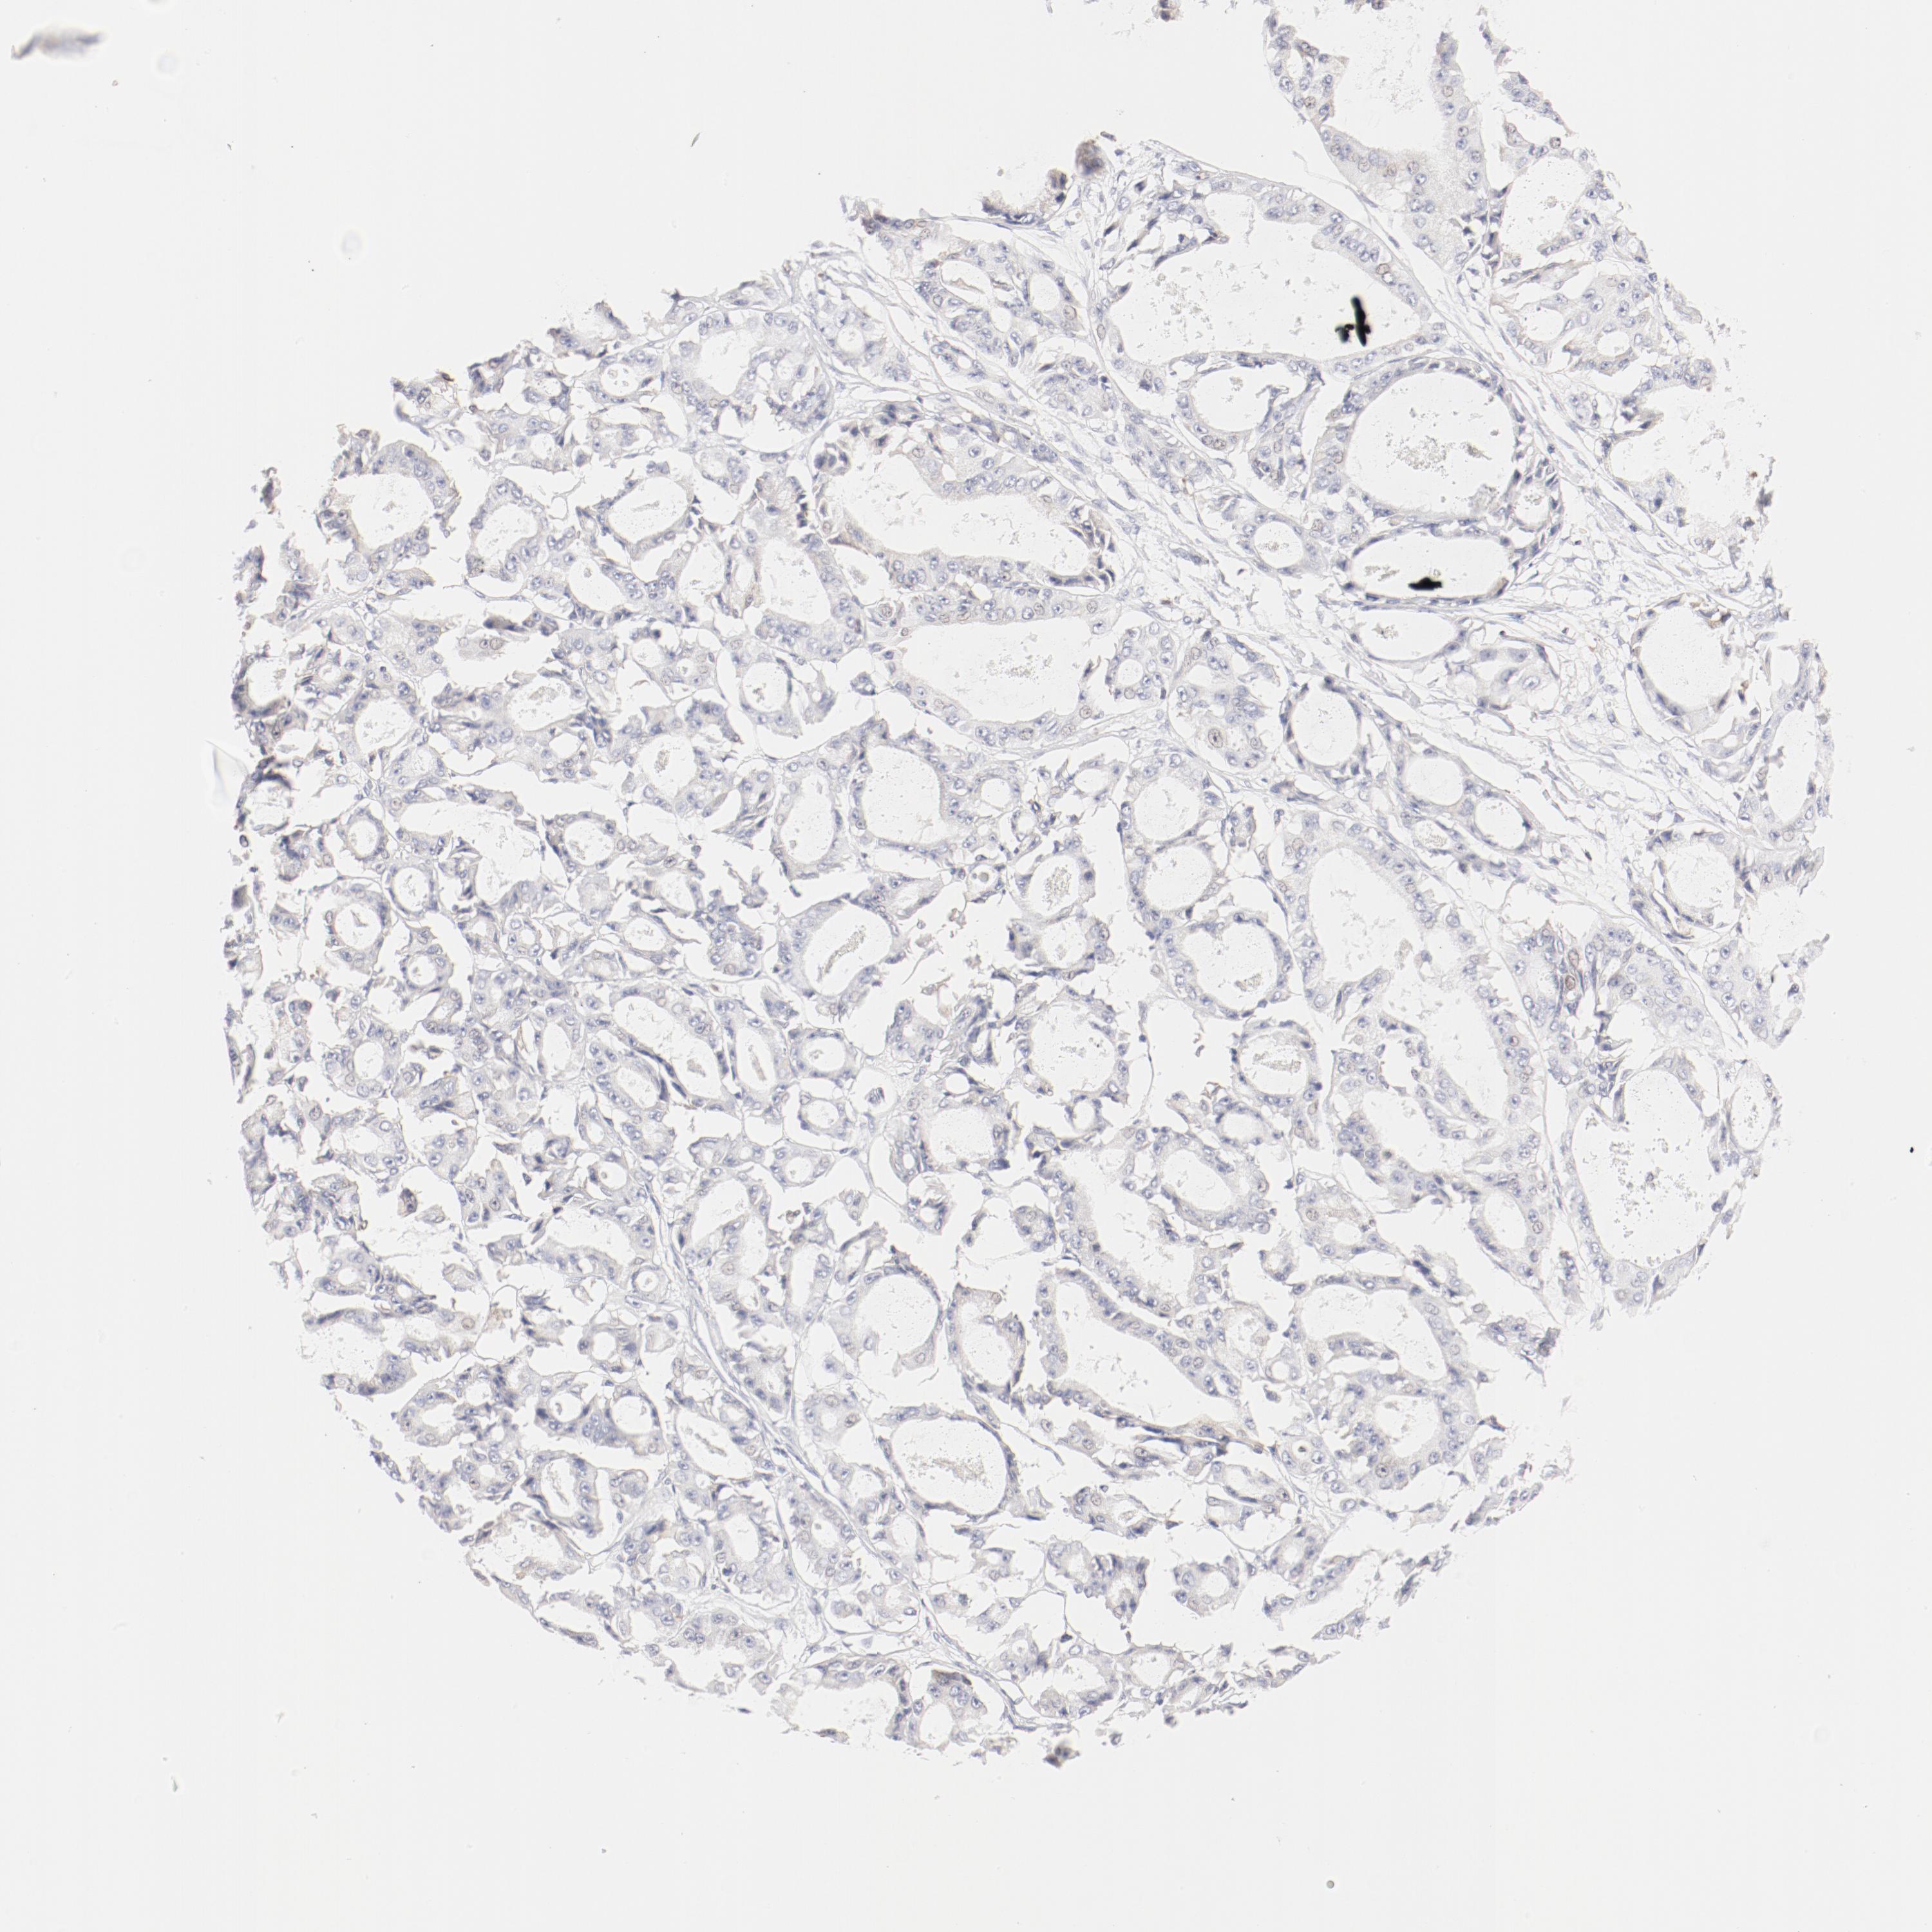

OVARIAN CANCER - Protein expressioni

A mouse-over function shows sample information and annotation data. Click on an image to view it in a full screen mode. Samples can be filtered based on level of antibody staining by selecting one or several of the following categories: high, medium, low and not detected. The assay and annotation is described here.

Note that samples used for immunohistochemistry by the Human Protein Atlas do not correspond to samples in the TCGA dataset.

Antibody stainingi

Antibody staining in the annotated cell types in the current human tissue is reported as not detected, low, medium, or high, based on conventional immunohistochemistry profiling in selected tissues. This score is based on the combination of the staining intensity and fraction of stained cells.

Each image is clickable and will lead to virtual microscopy that enables deeper exploration of all samples and also displays staining intensity scores, fraction scores and subcellular localization as well as patient and tissue information for each sample.

Antibody HPA003524

Antibody CAB000458

Cystadenocarcinoma, mucinous, NOS

Carcinoma, endometroid

Cystadenocarcinoma, serous, NOS